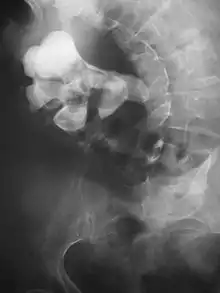

Otherwise a noncontrast helical CT scan with 5 millimeters (0.2 in) sections is the diagnostic method to use to detect kidney stones and confirm the diagnosis of kidney stone disease.[13][47][51][52][7] Near all stones are detectable on CT scans with the exception of those composed of certain drug residues in the urine,[53] such as from indinavir. Calcium-containing stones are relatively radiodense, and they can often be detected by a traditional radiograph of the abdomen that includes the kidneys, ureters, and bladder (KUB film).[53] Some 60% of all renal stones are radiopaque.[51][54] In general, calcium phosphate stones have the greatest density, followed by calcium oxalate and magnesium ammonium phosphate stones. Cystine calculi are only faintly radiodense, while uric acid stones are usually entirely radiolucent.[55]

Where a CT scan is unavailable, an intravenous pyelogram may be performed to help confirm the diagnosis of urolithiasis. This involves intravenous injection of a contrast agent followed by a KUB film. Uroliths present in the kidneys, ureters, or bladder may be better defined by the use of this contrast agent. Stones can also be detected by a retrograde pyelogram, where a similar contrast agent is injected directly into the distal ostium of the ureter (where the ureter terminates as it enters the bladder).[51]